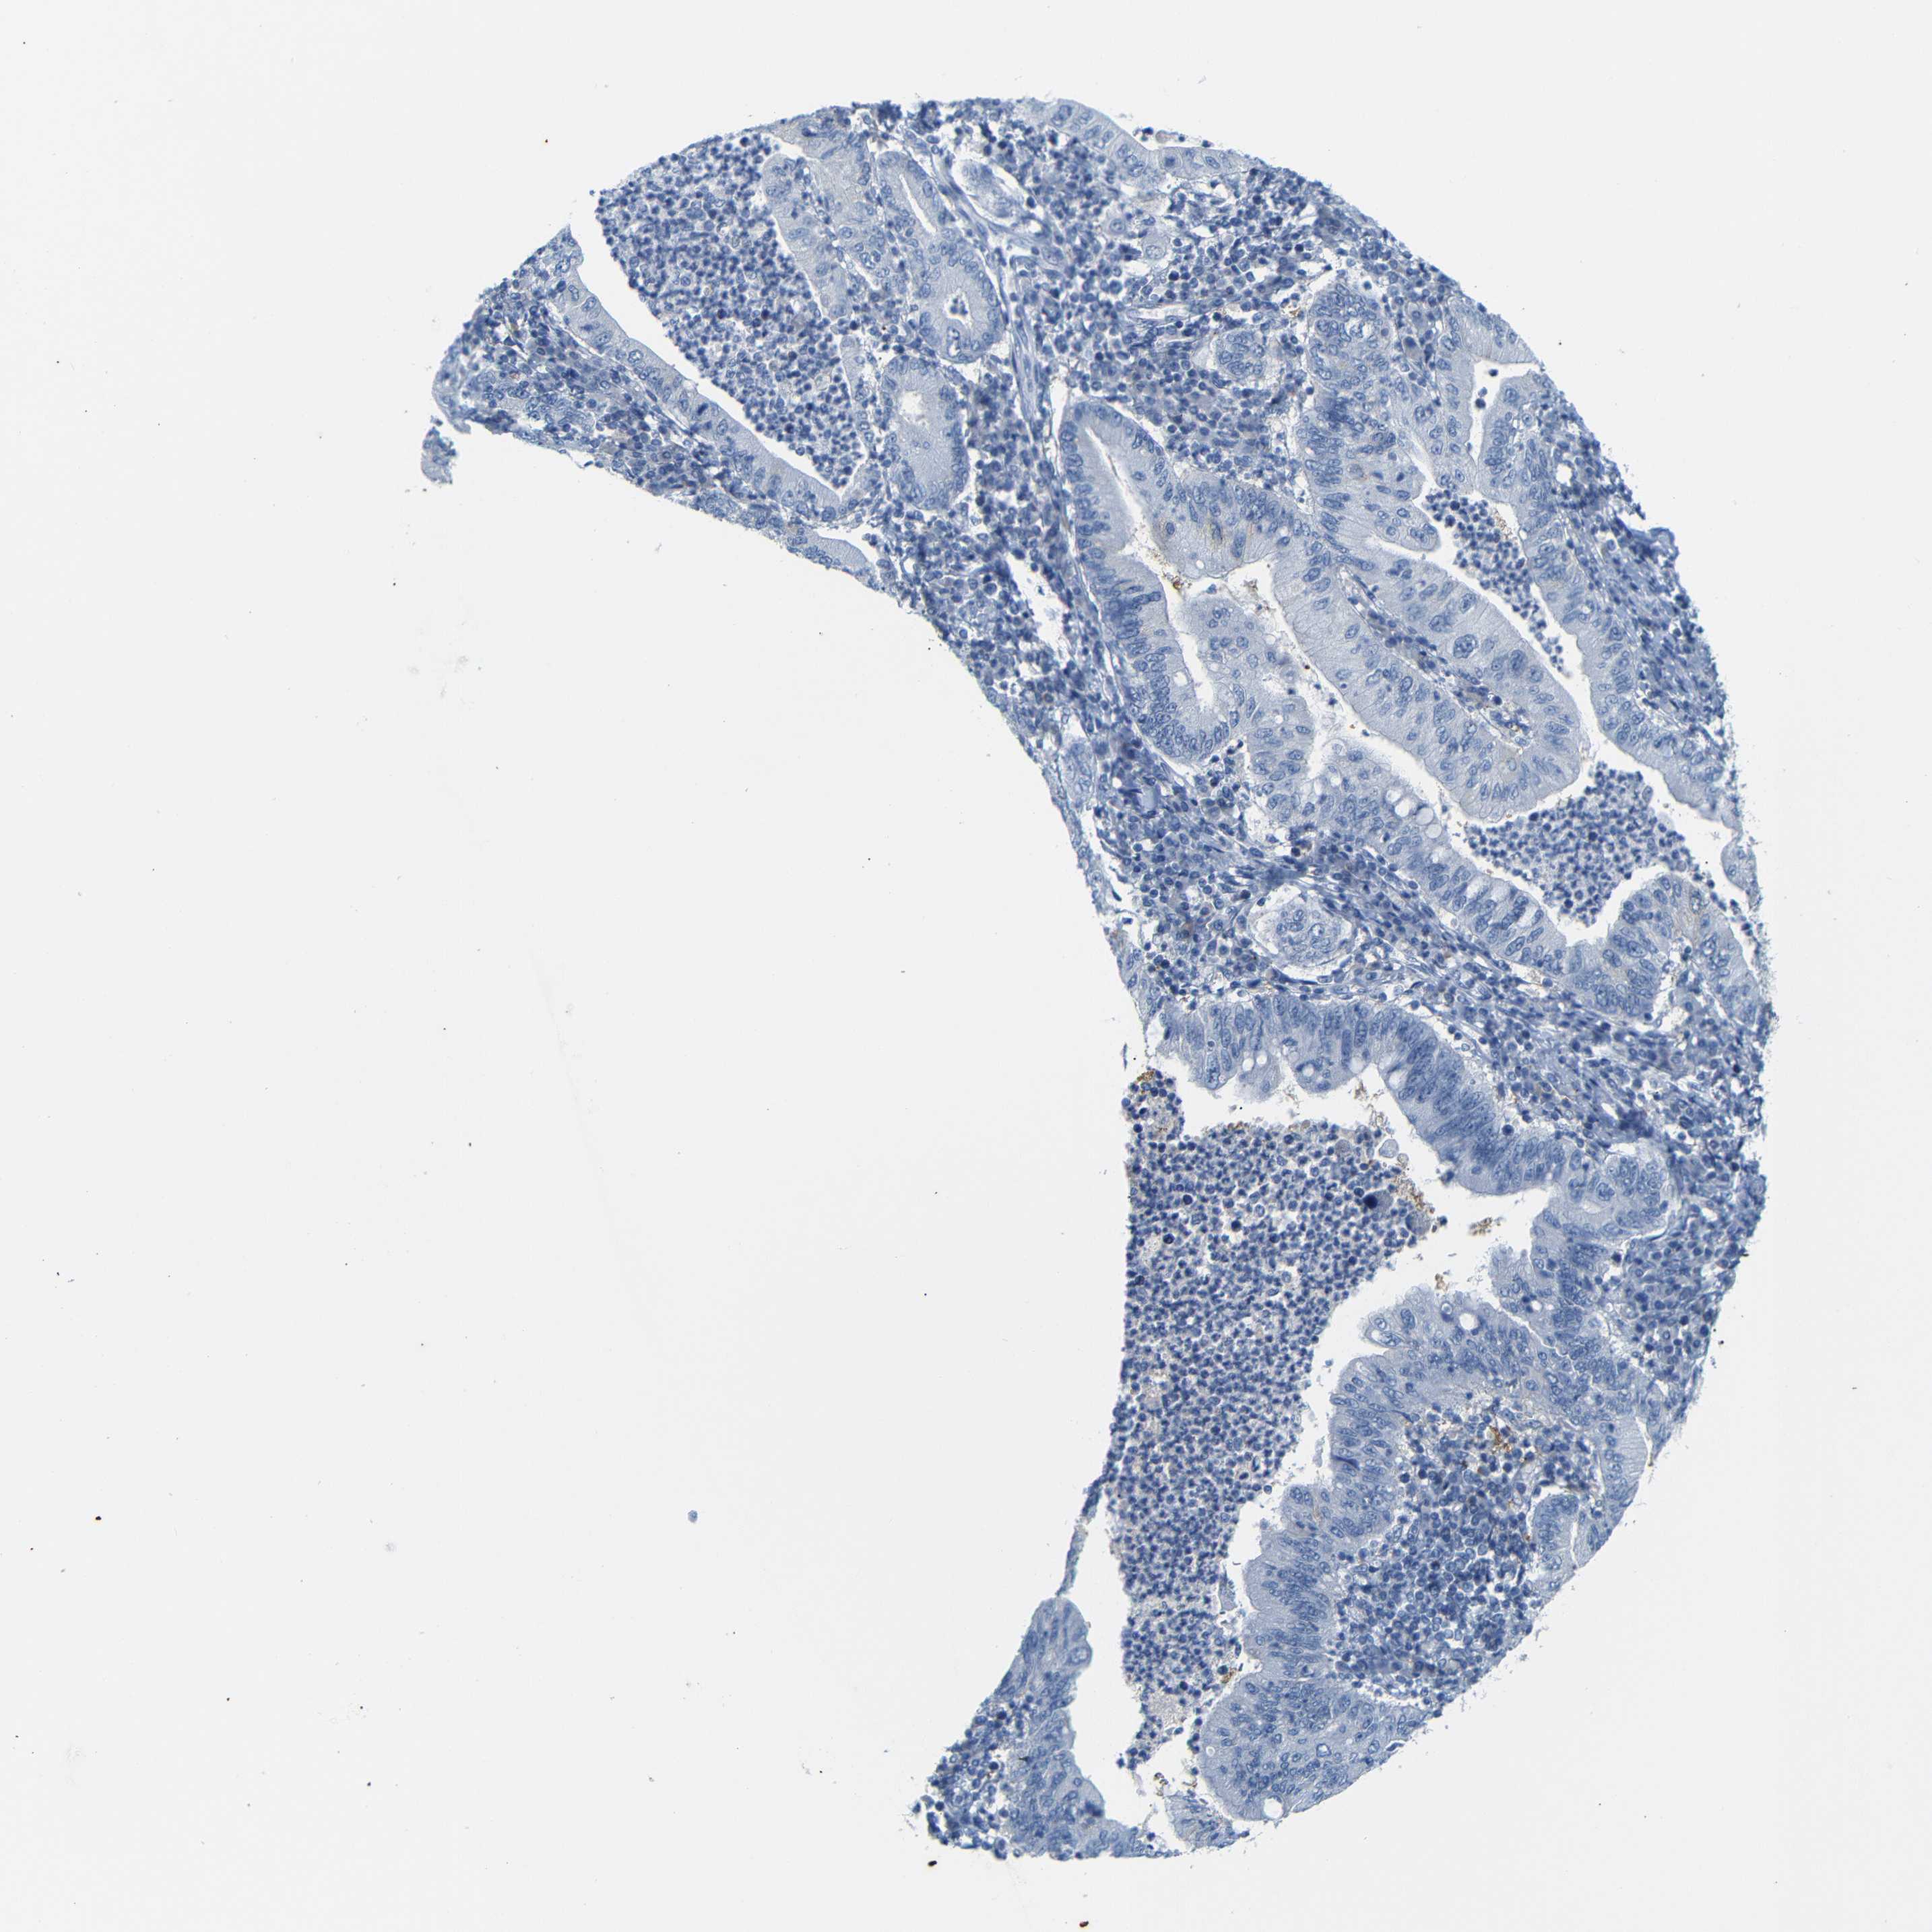

STOMACH CANCER - Protein expressioni

A mouse-over function shows sample information and annotation data. Click on an image to view it in a full screen mode. Samples can be filtered based on level of antibody staining by selecting one or several of the following categories: high, medium, low and not detected. The assay and annotation is described here.

Antibody staining in the annotated cell types in the current human tissue is reported as not detected, low, medium, or high, based on conventional immunohistochemistry profiling in selected tissues. This score is based on the combination of the staining intensity and fraction of stained cells.

Each image is clickable and will lead to virtual microscopy that enables deeper exploration of all samples and also displays staining intensity scores, fraction scores and subcellular localization as well as patient and tissue information for each sample.

Antibody HPA013323

Staining

High

Medium

Low

Not detected

Intensity

Strong

Moderate

Weak

Negative

Quantity

>75%

75%-25%

<25%

None

Location

Nuclear

Cytoplasmic/membranous

Cytoplasmic/membranous,nuclear

Adenocarcinoma, NOS

Adenocarcinoma, High grade